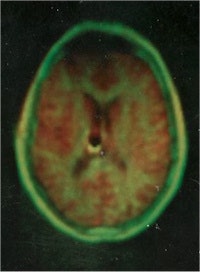

Figure 3: Early NMR of human head, 1980 (EMI). Image obtained with polar reconstruction similar to CT. The later images were improved by using the Cartesian (phase delay) reconstruction, as used today. Image courtesy of the archives of the British Institute of Radiology.

By 1978 Hugh Clow and Ian Young, working at EMI, reported the first transverse NMR image through the human head with rapid improvement of resolution (figure 3). More pioneering research was conducted at the University of Aberdeen under John Mallard. They developed the spin warp technique. Their team had published the first image through the body of a mouse in 1974. Peter Mansfield further developed the use of gradients in the magnetic field. He was a pioneer in the fast imaging techniques such as echo-planar imaging, which was introduced in the 1980s.